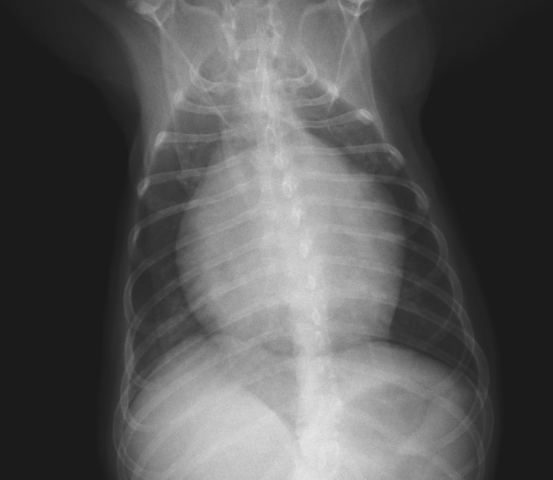

レントゲン検査では、大きく丸くなった心臓が確認できます。

こちらは正常な心臓です。